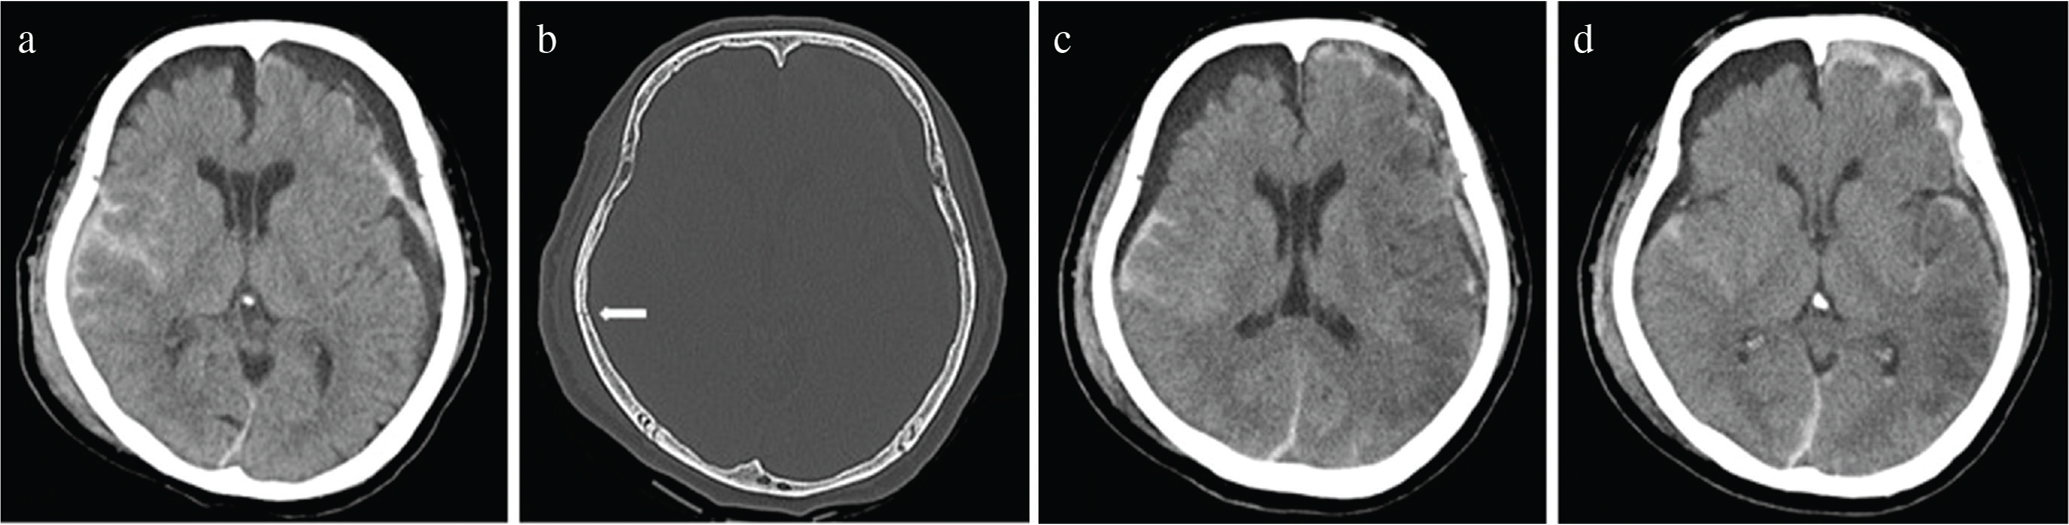

(a) Admission computed tomography (CT) scan showing diffuse traumatic subarachnoid hemorrhage of the whole cerebrum and a left subdural hematoma within a hygroma. (b) Bone-window CT scan shows a linear skull fracture (arrow) in the right temporoparietal region. (c and d) Five days after admission, plain CT showed multiple low-density areas in the left hemispheric cerebrum and slight brain edema with disappearance of the subdural hematoma.